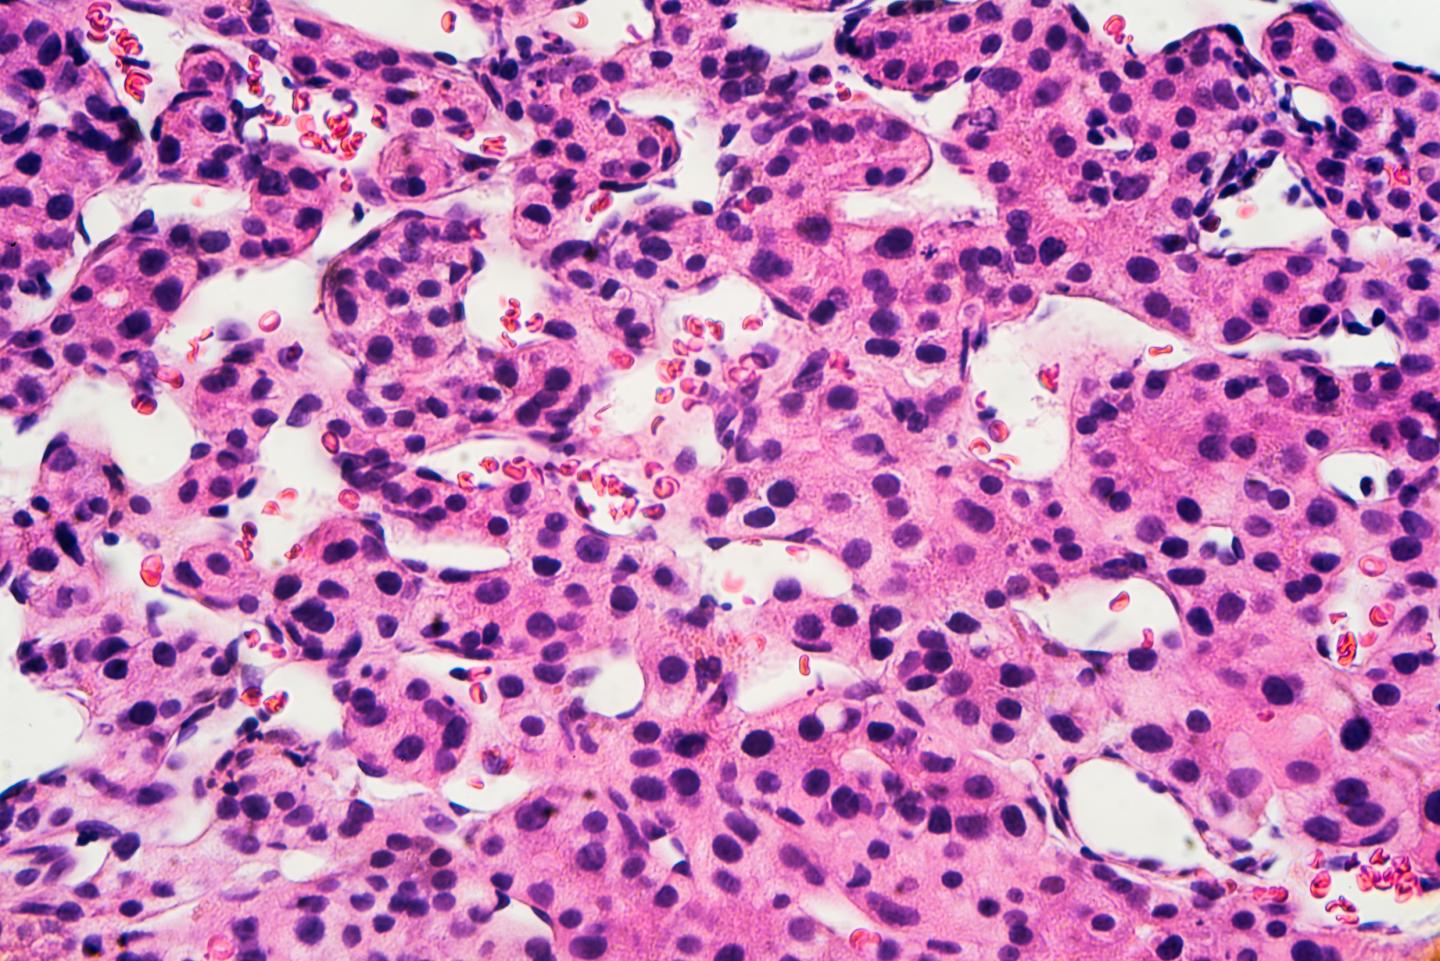

image: Microscopic image of hepatocellular carcinoma view more

Parmi tous les virus de l’hépatite, le D est le plus mal connu. En effet, ce petit virus, qui ne peut infecter que les personnes déjà atteintes par l’hépatite B, n’a jusqu’ici été que peu étudié. Or, l’hépatite D constitue l’une des formes les plus dangereuses d’hépatite virale chronique à cause de son évolution possible vers des affections irréversibles du foie (cancer et cirrhose, notamment). Des scientifiques de l’Université de de Genève (UNIGE) et des Hôpitaux universitaires de Genève (HUG) se sont penchés sur la conséquence la plus grave de l’hépatite chronique: le carcinome hépatocellulaire, un cancer du foie particulièrement agressif et souvent mortel. En menant une revue systématique de la littérature et en effectuant une méta-analyse de toutes les données disponibles, ils démontrent que les personnes infectées par le virus de l’hépatite D ont un risque jusqu’à trois fois plus élevé de développer un carcinome hépatocellulaire que celles infectées uniquement par le virus l’hépatite B. Ces résultats, à lire dans le Journal of Hepatology, plaident pour un dépistage systématique de l’hépatite D chez les patients atteints d’hépatite B afin, d’une part, de mieux prendre en charge les patients, et, de l’autre, de mieux appréhender la prévalence réelle de la maladie.